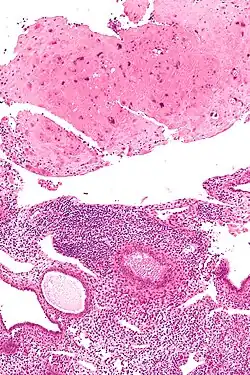

| Micrograph of a placental site nodule (top of image). H&E stain. |

A placental site nodule (PSN) is benign remnant from a previous pregnancy.[1]

PSNs are intermediate trophoblastic remnants.

Typically, they consist of pink (hyaline) material using the standard stain and contain few cells. Bizarre multinucleated cells may be present; however, there is no mitotic activity. The differential diagnosis includes (cervical) squamous cell carcinoma, gestational trophoblastic disease, and exaggerated placental site.